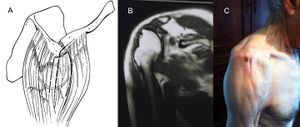

In the most severe conditions, part or all of the deltoid muscle may be completely absent. Such permanent impairment is rare but may be observed following deltoid muscular flap transfer (for irreparable rotator cuff tears, Figure)[105][106][107] or following tumor resection (Figure).

Status after a left deltoid muscular flap transfer for irreparable rotator cuff tears. A: Schematic drawing of the surgical technique (with permission of Gazielly D.). B: Frontal magnetic resonance imaging demonstrates absence of the deltoid muscle laterally. C. Clinical photo demonstrating atrophy of the anterior and middle deltoid.